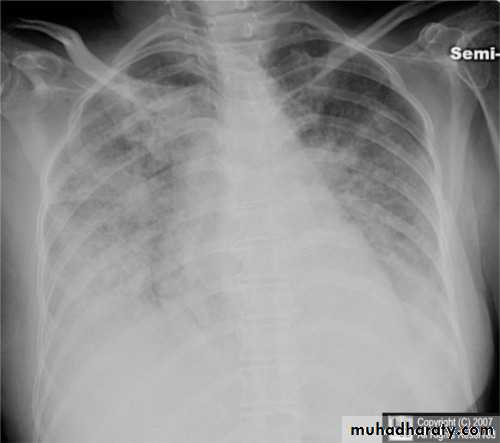

Interstitial pulmonary edema

Pulmonary edema ( alveolar pulmonary edema)

38.interstial pulmonary edema

39.pulmonary edema ( alveolar pulmonary edema )